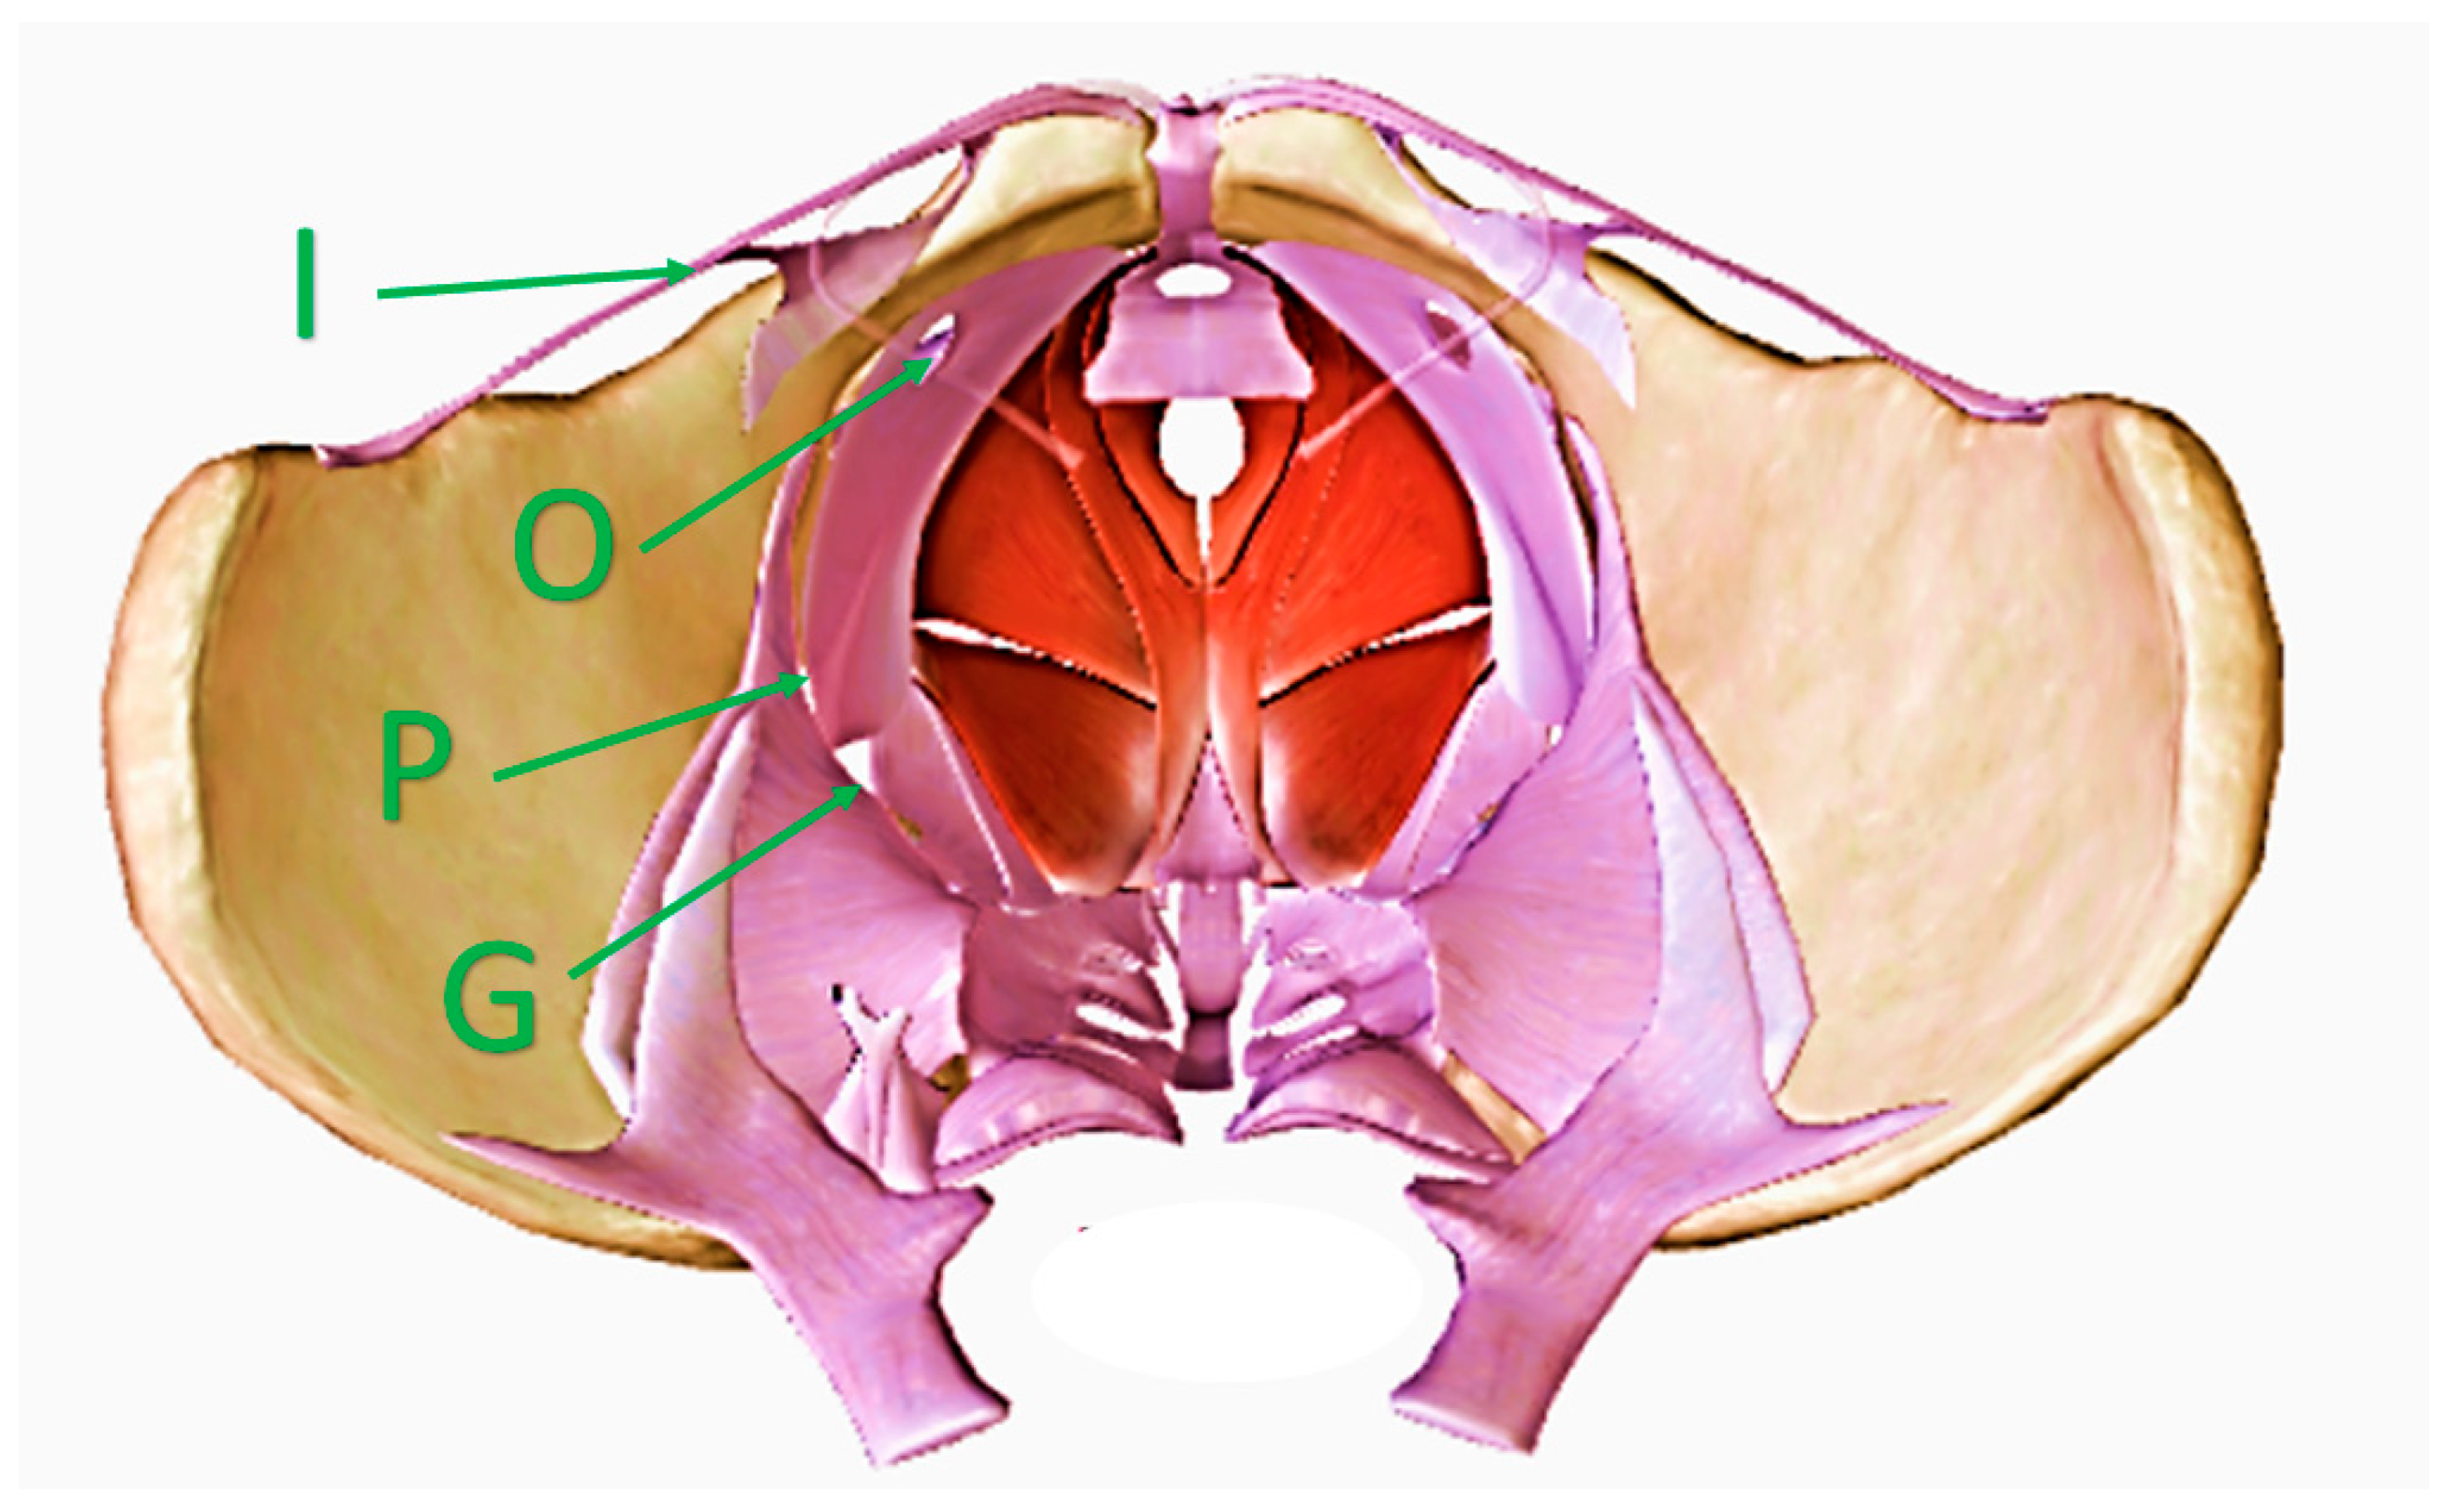

Although pelvic escape points are primarily assessed from the perineum and groin, their anatomy from the pelvic side should also be acknowledged. Importantly, venous plexuses in the pelvis are separated from the veins located in the perineal, inguinal, and gluteal areas by the sacrum and pelvic bones, and associated muscles, fibrous membranes, and ligaments. In addition to the main physiologic pathway, which is located under the inguinal ligament, there are only a few narrow routes providing connections between the intra- and extra-pelvic veins in the settings of pathology.

These additional pathways can become dilated, particularly during pregnancy, and can facilitate the development of extra-pelvic VVs. In the females presenting with normal anatomy, there are four such openings in the floor of the pelvis: the lesser sciatic foramen, where the internal pudendal veins enter the pudendal canal, the greater sciatic foramen (particularly its infrapiriform part), the deep inguinal ring, and the obturator foramen (Figure 1). Out of these four locations, the lesser sciatic foramen, which facilitates communication alongside the internal pudendal veins, is of particular clinical interest, because a majority of VVs of pelvic origin are associated with this opening in the pelvic floor. Venous refluxes originating at the greater sciatic foramen are often associated with anatomical variants resulting from incomplete rebuilding of the fetal pattern of the lower limb veins. The route through the inguinal canal is primarily associated with venous hypertension in the pelvis. The route through the obturator foramen is probably the least understood. The obturator veins join the tributaries of the profunda femoris vein (the deep vein of the thigh). All these veins are situated inside the medial fascial compartment of the thigh. Current anatomical textbooks do not describe the important connections of these veins with the superficial veins in the groin or perineum. On the other hand, VVs associated with incompetent obturator veins are well known. Obviously, more good quality research is needed regarding this topic.

Figure 1. Female pelvis seen from above, with openings in the pelvic floor and veins providing communication with the perineum, gluteal area, and the lower limb. I—the inguinal canal through the veins of the round ligament of the uterus; O—the obturator foramen through the obturator veins; P—the lesser sciatic foramen through the internal pudendal veins; G—the greater sciatic foramen through the gluteal veins.